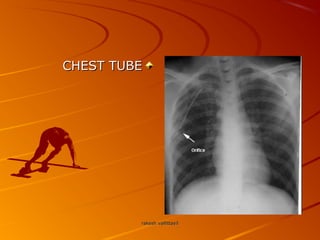

CHEST TUBECHEST TUBE

CHEST TUBECHEST TUBE rakeshvallittayilrakesh vallittayil